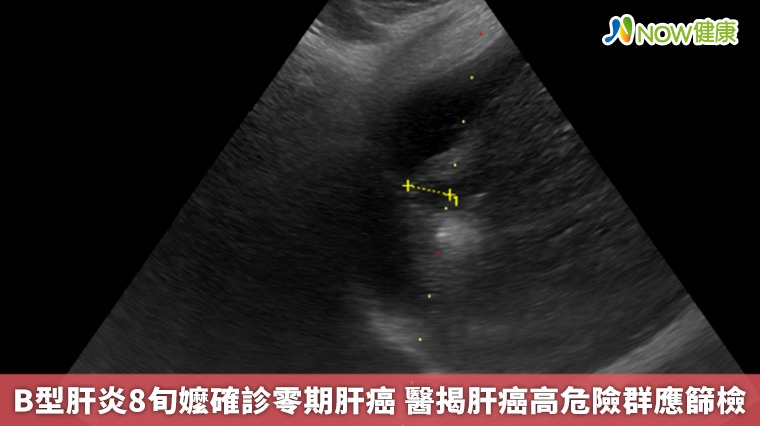

【NOW健康 林郁敏/新北報導】一名83歲的黃姓老婦人因身體不適到台北慈濟醫院就診,就診過程中意外發現肝功能異常,進一步檢查發現一顆約1.5公分的肝臟腫瘤,確診為第零期肝癌,同時也發現患者患有B型肝炎,卻因沒有症狀所以不曾進行相關治療。所幸發現及時,由胃腸肝膽科醫師鄭煜明執行電燒治療,術後三天患者順利出院,目前僅需定期追蹤避免復發。

▲台北慈濟醫院胃腸肝膽科醫師鄭煜明提醒,肝臟疾病通常在初期難以發現,容易錯過治療佳機,建議45歲以上民眾終生主動接受一次B、C型肝炎篩檢。(圖/台北慈濟醫院提供)

根據臨床數據,零期肝癌治療後平均存活率超過10年以上,若延誤至第二期則縮短為約5年,第三期降至2.5年,若已轉移,存活時間僅剩半年。「在第零期使用電燒治療普遍可根治,不需要化療,已經有遠處轉移才會考慮使用免疫療法及標靶治療。」鄭煜明醫師解釋,電燒治療是透過超音波導引定位,使用電極產生電流,造成離子震動產生超過60度的熱能氣化腫瘤,比起手術能更完整保留健康的肝臟組織。